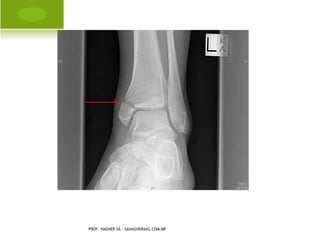

   ENTORSE: lesão aguda do ligamento,

causando perda temporária da

congruência articular, causado por

trauma indireto.

Grau I  não há ruptura, apenas um

esgarçamento.

Grau II  ruptura parcial.

Grau III  ruptura total.

PROF. VAGNER SÁ - SAVAGNER@IG.COM.BR